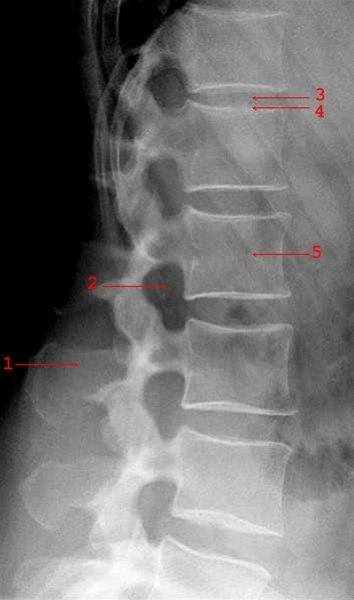

Normalt sidebilde av de lumbale virvler (Ryggsøylen, nedre del)

- Processus spinosus

- Foramen intervertebrale

- Mellomvirvelskive (litt lav)

- Øvre dekkplate L1

- Virvelcorpus L2